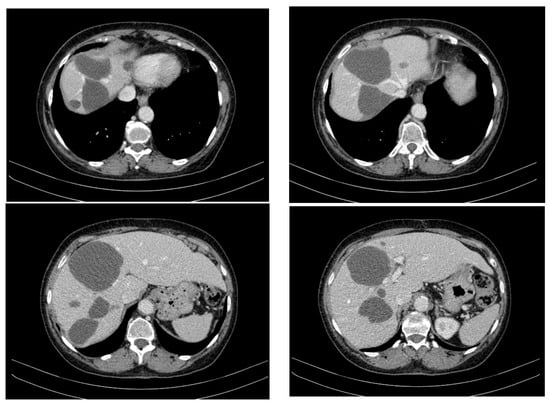

A CT evaluation after 7 months of sunitinib therapy showed stable hepatic disease, with no new metastatic lesions (Figure 4). However, the patient experienced significant side effects, including Grade 3 neutropenia and hypertension, leading to temporary treatment interruptions. Other reported side effects included cataract development, complete nail bed dekeratinization of the toes, and persistent anaemia, for which she received supportive therapy.

Figure 4.

CT appearance at 7 months of treatment with sunitinib.

At 20 months on sunitinib (85 months post-diagnosis), a new cystic lesion in segment VII was detected, raising concerns about treatment resistance (Figure 5). While some known lesions had slightly decreased in size, the emergence of this new lesion indicated ongoing tumour activity that required close monitoring and possible re-evaluation of the treatment strategy.

Figure 5.

CT appearance at 20 months of treatment with sunitinib.